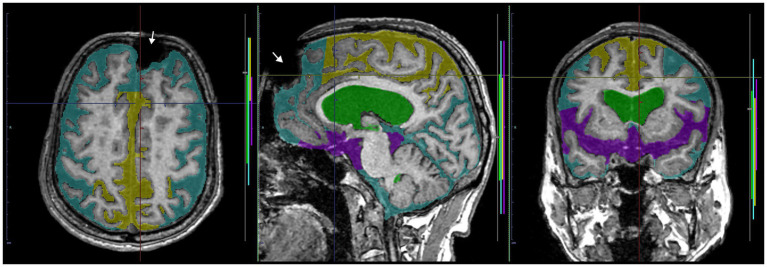

Preparation for data processing of deep learning

As ground truth labels in our AI models, input image masks for volumetric semantic segmentation on the 3D T1-weighted MRI were created by combining manual segmentation with the 3D Viewer and fully automatic segmentation with the Brain Subregion Analysis applications (Figures 1A–C) on an independent 3D volume analyzer workstation (SYNAPSE 3D; FUJIFILM Corporation, Tokyo, Japan). In the Brain Subregion Analysis application, intracranial spaces were segmented fully automatically into 26 subregions including ventricles and SAS within 1 min (ref. Yamada et al., 2023c). The input image masks from 3D T2-weighted MRI were also created using our original method, combining a simple threshold algorithm and manual segmentation (Figures 1D–F), as previously reported (ref. Yamada et al., 2015, ref. 2016a,ref. b). Total SAS were further segmented into the Sylvian fissure and basal cistern, and the high-convexity SAS, which was defined as the location above the body of the lateral ventricles, with the lateral end 3 cm from the midline, the posterior end in the bilateral posterior parts of the callosomarginal sulci, and the anterior end on the coronal plane perpendicular to the AC–PC line passing through the front edge of the genu of the corpus callosum (Figure 2; Supplementary Videos S1–S4) (ref. Yamada et al., 2023a). All input image masks as the ground truth labels were transferred to the SYNAPSE Creative Space for cloud-based AI development service (FUJIFILM Corporation). All masks were processed and formatted into a form that could utilize the training or inference process. Regarding the output of the inference process, feature maps were obtained. Overall, 159 T1-weighted images were assigned to 110 images for training, 30 for internal and 19 for external validation (test), and 180 T2-weighted images were assigned to 130 images for training, 30 for internal validation and 20 for external validation. Inference was performed in the images for internal validation and external validation.

Volumetric semantic segmentation

Training and internal validation of the 3D U-Net model for semantic segmentation were repeated over 1,000 times (Figures 4–7; Supplementary Figures S1, S2). Overall, the intracranial CSF space, total ventricles, total SAS, Sylvian fissure and basal cistern, and the high-convexity SAS were segmented fully automatically from 3D T1-weighted (Figure 8) and T2-weighted MRIs (Figure 9). There was no significant difference between manually and automatically segmented volumes of the total ventricles, total SAS, high-convexity SAS, and Sylvian fissure and basal cistern (Table 3). Among the segmented regions, the mean Dice scores for the total ventricles were highest (0.85 from T1 and 0.83 from T2), those for the Sylvian fissure and basal cistern were second highest (0.70 and 0.69), and those for the high-convexity SAS were lowest (0.68 and 0.60). The mean Dice coefficient scores for all of the regions segmented from the T1-weighted image were superior to those from the T2-weighted image. The mean differences between the manually and automatically segmented volumes of the high-convexity SAS were smaller (T1 and T2; 3.6 mL and 4.2 mL) than those of the Sylvian fissure and basal cistern (5.3 mL and 8.3 mL).